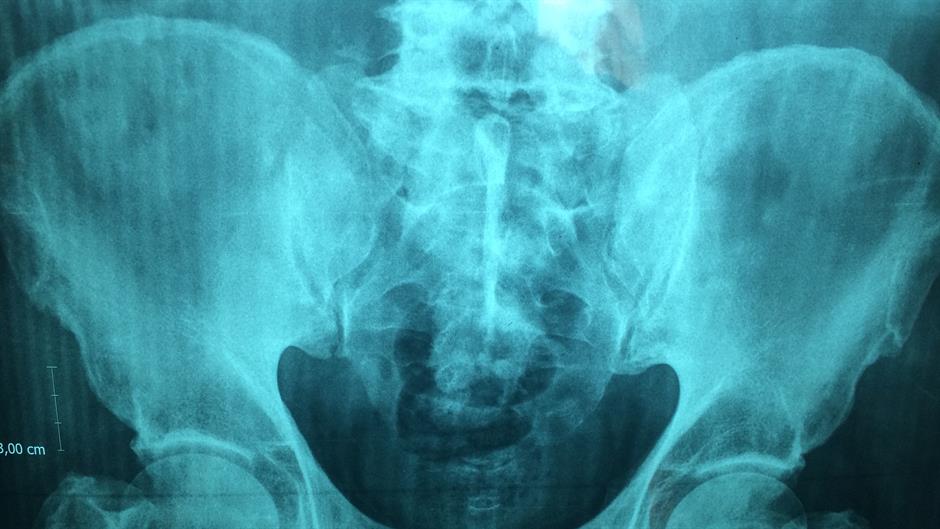

Novi organ nazvan je Mezenterij, nalazi se u našem probavnom sistemu te se dugo mislilo kako se sastoji od fragmentiranih i odvojenih struktura. No, posljednja istraživanja pokazala su da se zapravo radi o jednom sasvim novom organu.

Pred ljekarima i studentima medicine velik je zadatak, a to je pronaći funkciju novog organa i otkriti koju ulogu mezenterij ima kada su u pitanju bolesti abdomena, piše ScienceAlert.